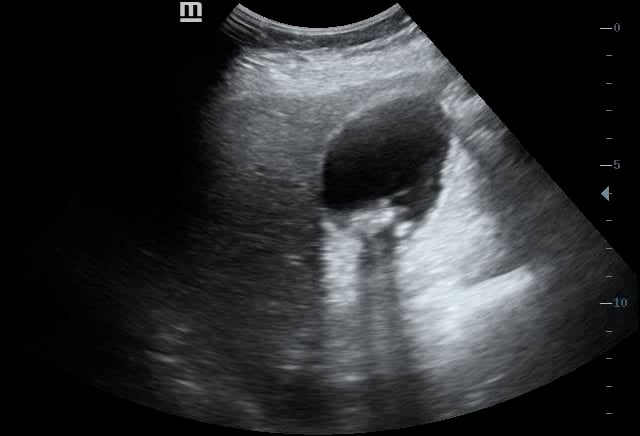

Gallbladder wall thickening, in abdominal ultrasound, indicates an abnormal increase in the thickness of the gallbladder wall, a key diagnostic finding in various medical conditions. This thickening can be a significant sign of inflammation, such as acute cholecystitis, where the gallbladder becomes acutely inflamed due to gallstones obstructing the cystic duct. Understanding this sonographic sign is crucial for prompt and accurate diagnosis in abdominal imaging.

Beyond acute cholecystitis, gallbladder wall thickening may also suggest other conditions like chronic cholecystitis, ascites, hypoalbuminemia, or even adjacent liver disease. Ultrasound is the primary imaging modality for evaluating gallbladder wall thickness, offering a non-invasive and effective way to assess the patient’s abdominal health. Early detection through precise ultrasound examination aids in timely medical intervention and improved patient outcomes.